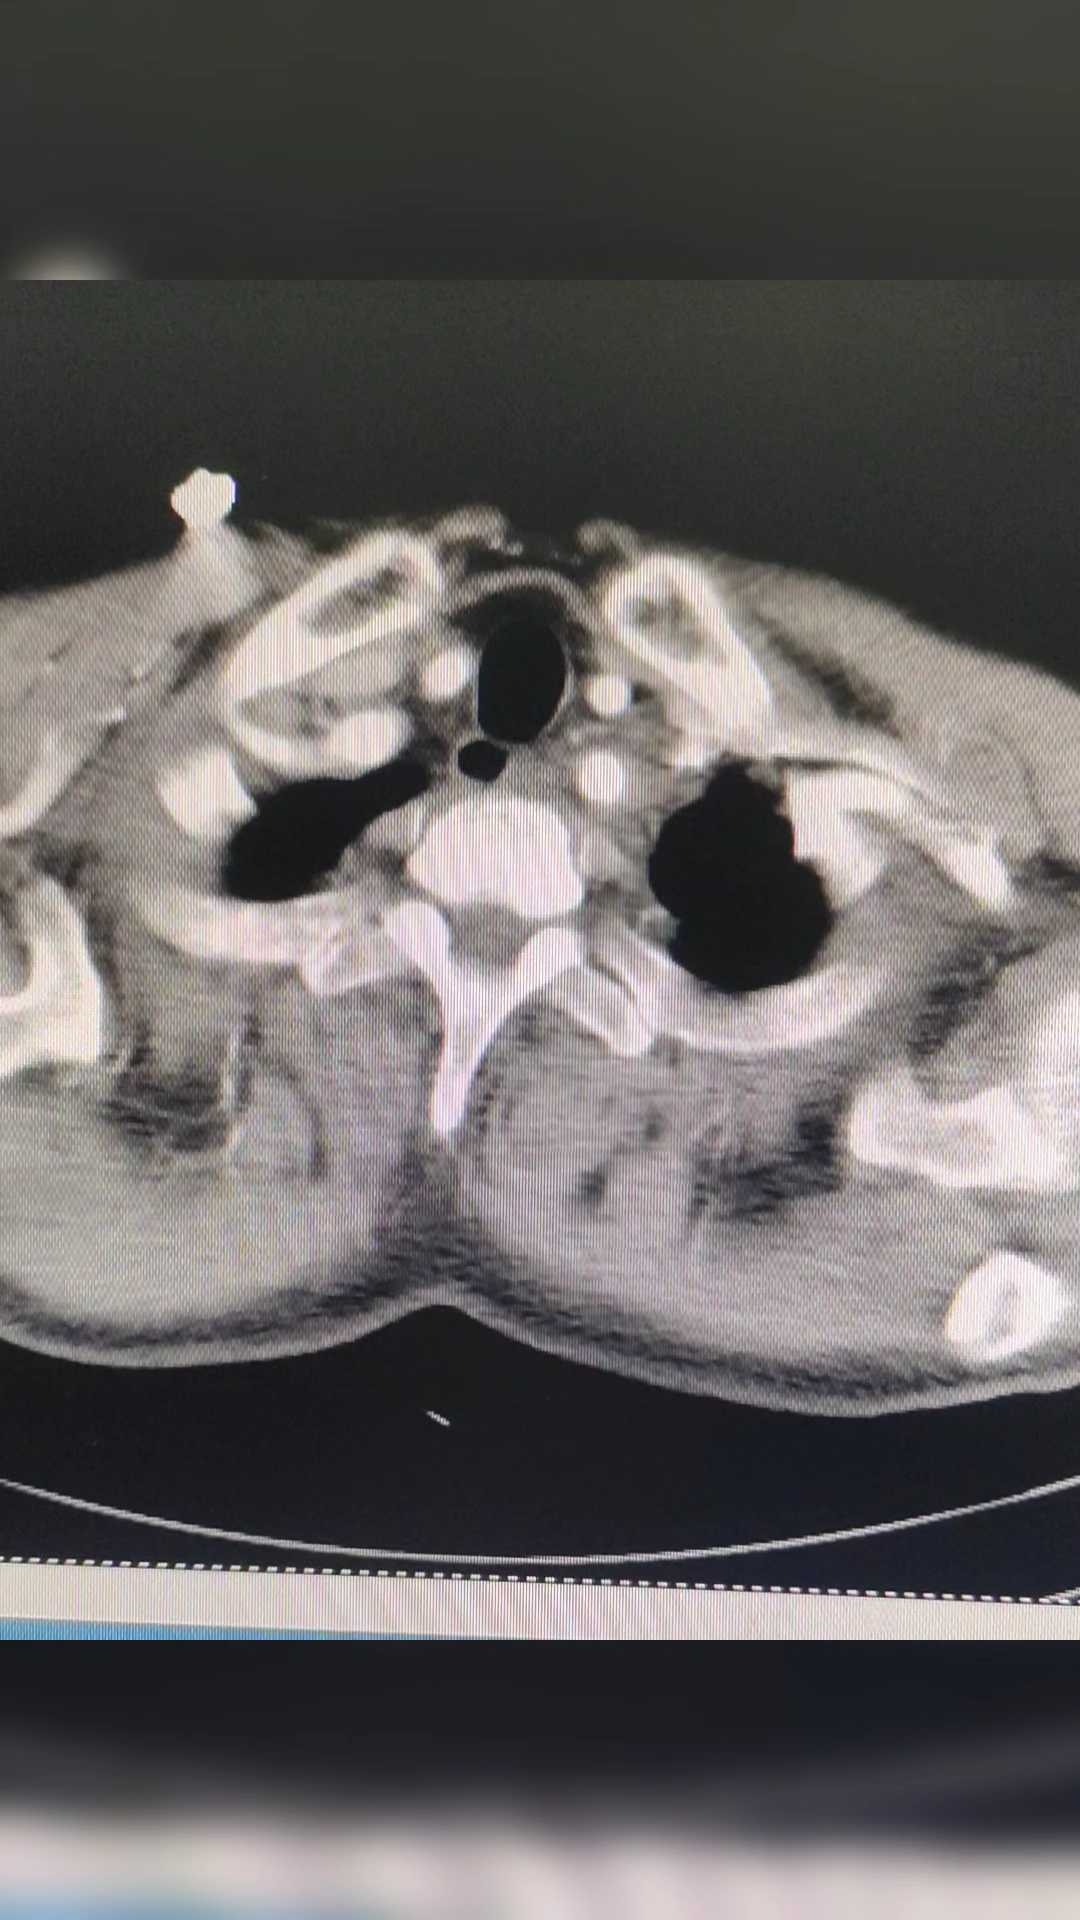

看过CT,园友们能看出是什么病吗?

主动脉夹层!

这个结果,是不是有点意外?因为症状不典型,如果不查CT,只按心脏的问题处理,那就麻烦大了!

急性 主动脉夹层 最典型症状为突发性剧烈胸/背疼痛,通常会伴有低血压和休克,其他特征性临床表现为心包积液、主动脉瓣反流和冠状动脉受累等。但是这个患者的胸痛不是很重,也没有低血压,双上肢的血压也没有明显的差距!特征性的表现,也就是心包积液了!